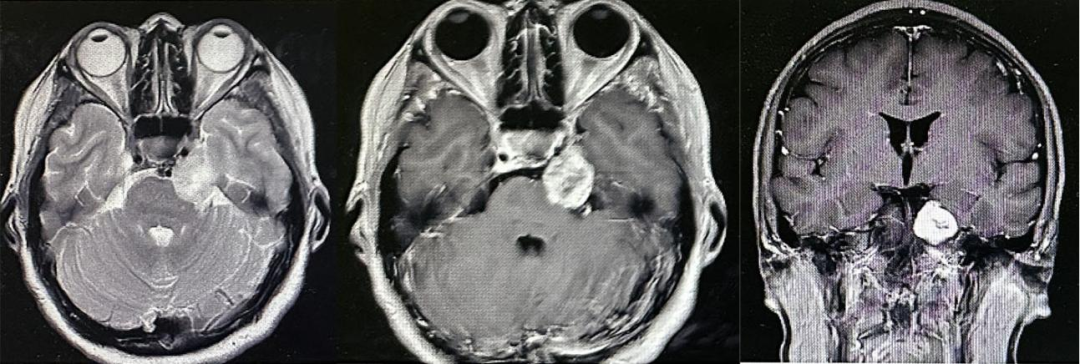

当出现面部不适时,许多患者会先就诊于口腔科或神经内科。但要确诊三叉神经鞘瘤,头颅MRI(磁共振成像)是重要的检查方法。

为什么 MRI 更准确?因为 CT 对软组织的分辨能力较弱,而 MRI 能清晰显示三叉神经的走行、肿瘤的大小、位置及是否压迫周围神经、脑组织,能精准定位肿瘤,为后续治疗方案的制定提供关键依据。

张先生正是通过头颅 MRI,明确了左侧三叉神经鞘瘤的大小和位置(未侵犯脑干),为后续手术治疗争取了最佳时机。